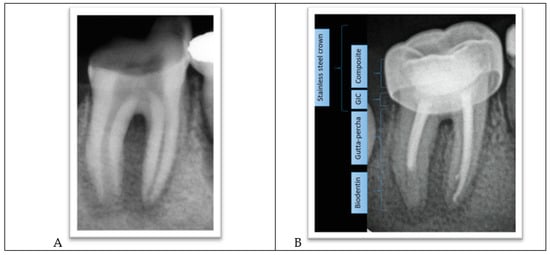

- The procedure involved local anesthesia, a rubber dam, and removal of caries.

- Working length was established using a radiograph.

- Copious irrigation with 2.5% sodium hypochlorite NaOCl, followed by minimal mechanical instrumentation of the root canal walls and additional irrigation with Q-mix (Dentsply Sirona) and ultrasonic activation was performed.

- Mesial canals were obturated with gutta-percha using a lateral condensation technique while the distal root was treated with MTA as an apical plug because there was no apical stop.

- A moist cotton pellet was placed in the canal to facilitate MTA setting, and the access cavity was restored using a glass ionomer cement.

- The next day, the setting of the MTA plug was verified, and the remaining portion of the root canal was filled with gutta-percha using lateral condensation. The pulp chamber was cleaned and the coronal access double-sealed with a bonded resin composite.

- A stainless steel crown was inserted.